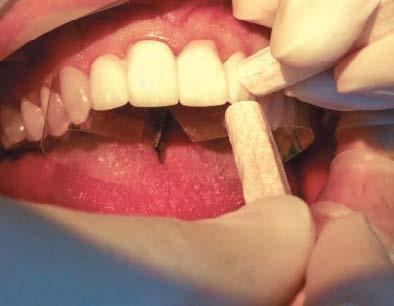

Cita 3. Entrega de las restauraciones finales

Comencé la cita de entrega de las restauraciones finales probando las carillas centrales y después continué trabajando hacia los laterales. Luego de confirmar que el ajuste era preciso, le ofrecí al paciente la oportunidad de mirarse al espejo, los retiré y procedí con la limpieza de la superficie interior de las restauraciones (Figura 11).

Después de haber descontaminado y aplicado Monobond® Plus (Ivo clar Vivadent; Amherst, N.Y.) a las

superficies internas de las restaura ciones, comencé por grabar en áci do el esmalte de las superficies con la ayuda de un gel etchant con un con tenido en ácido fosfórico del 37.5%, durante 15 segundos. Luego enjuago y seco las superficies por completo. En el esmalte seco, froté OptiBond™ Universal, adhesivo universal (Kerr Corporation; Brea, Calif.), luego

Comenzando por los centrales segui dos de los laterales, usé el cemento dental adhesivo de resina universal NX3 Nexus™ Tercera Generación (Kerr Corporation) para cementar las restauraciones en las preparaciones, dándome el tiempo suficiente para

posicionar correctamente las restau raciones. Me tomé unos minutos para limpiar cualquier exceso de cemen to antes de sellar las carillas con luz ultravioleta en su lugar (Figura 13).